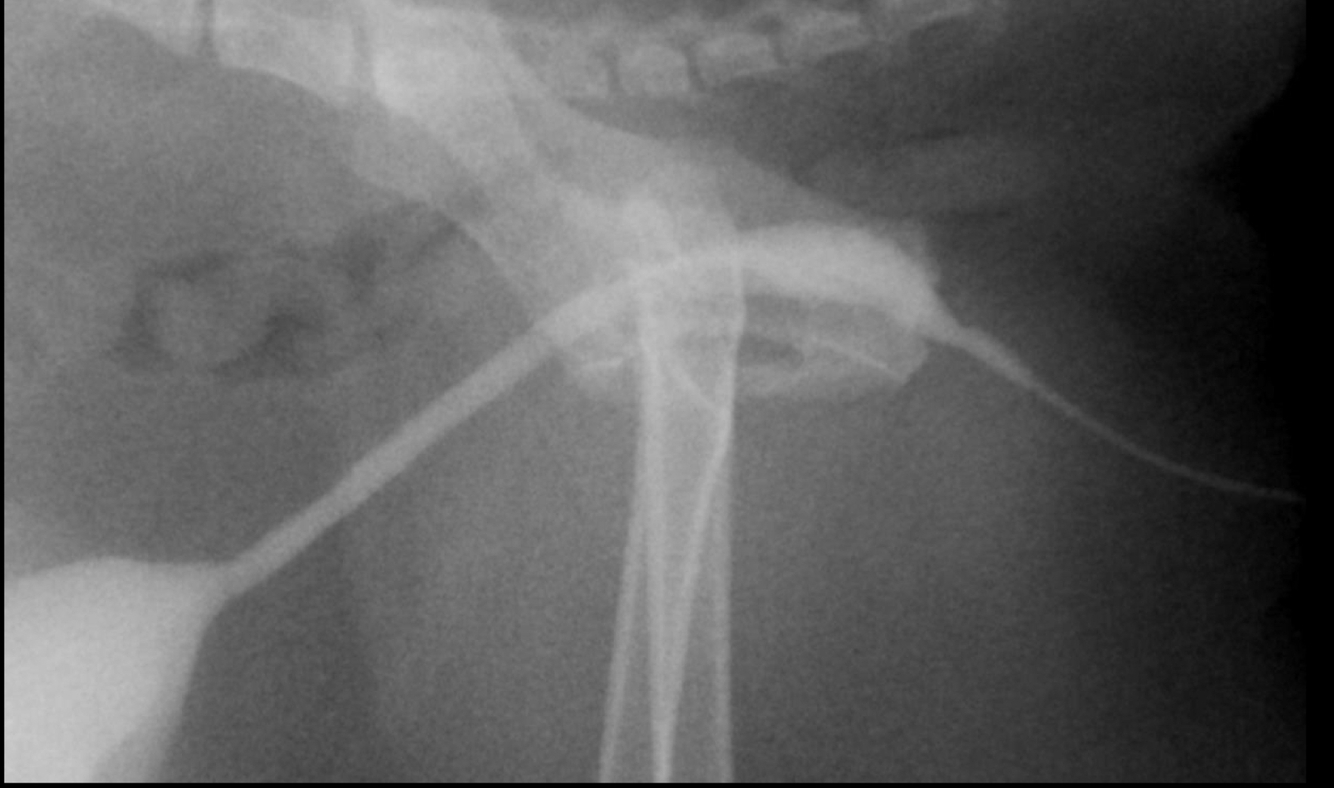

Feline fluoroscopic urethrogram:

broadly distended